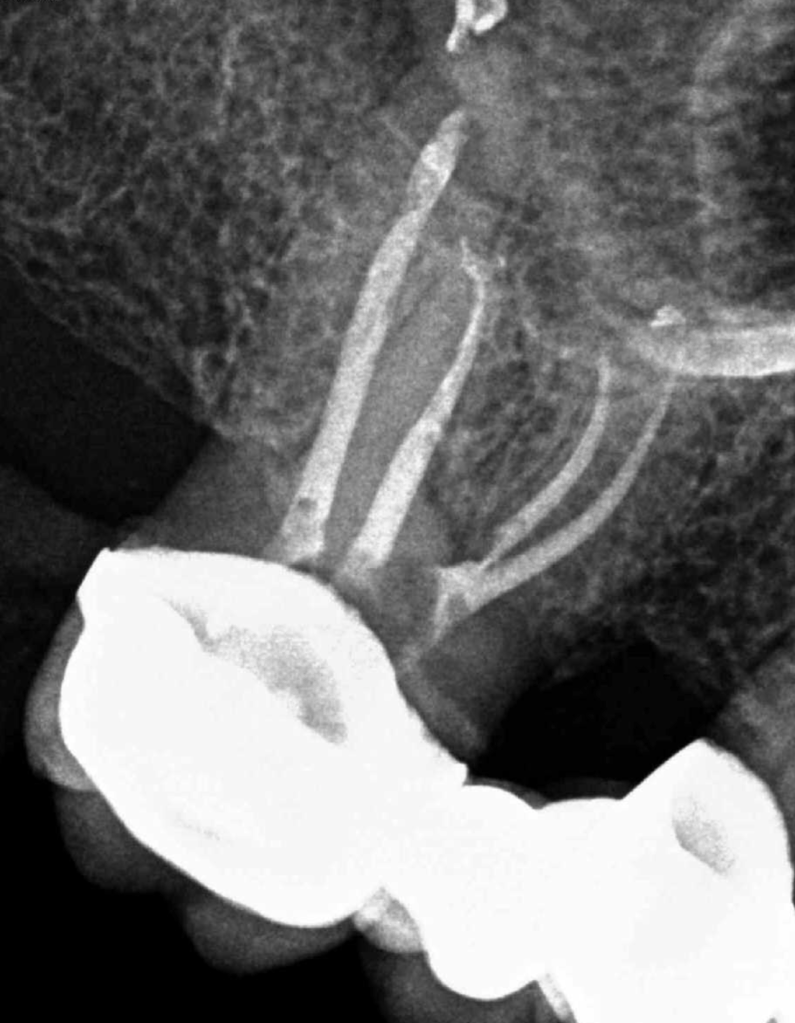

Endodoncias a traves de coronas

20 molar superior a traves de corona